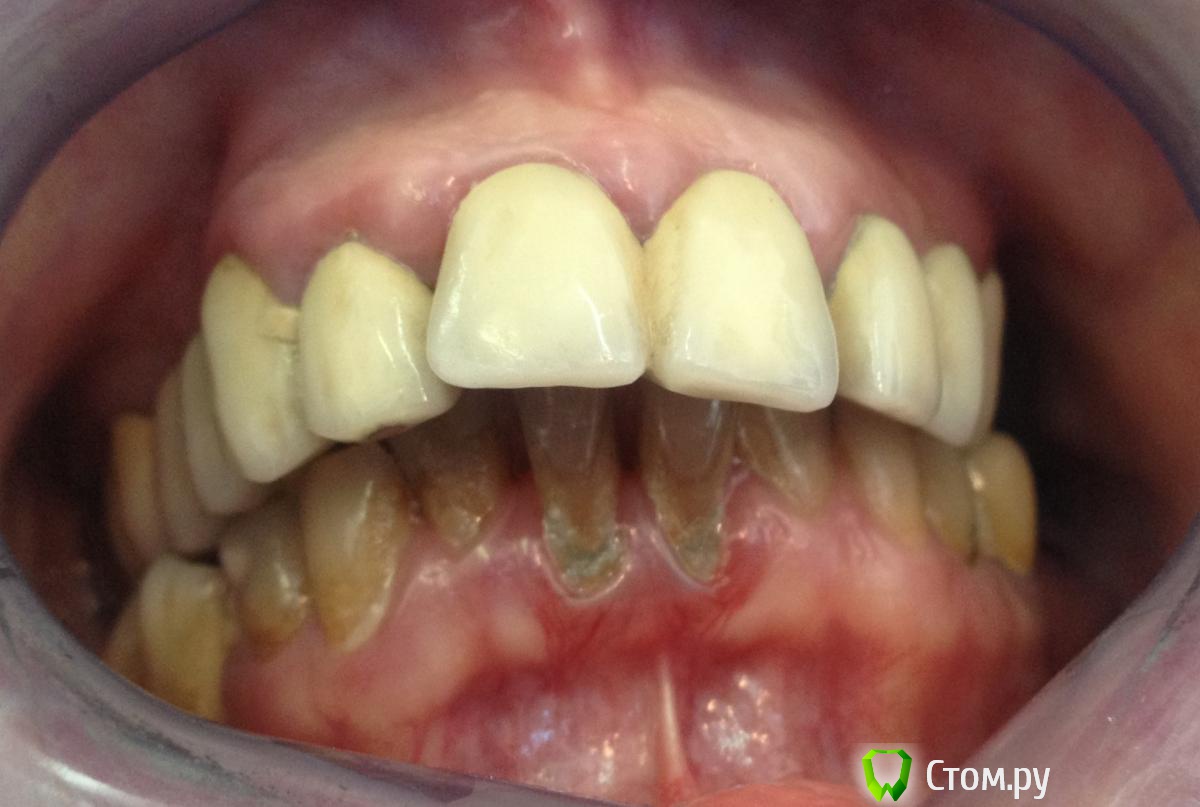

MaxDok Опубликовано 31 января, 2014 Поделиться Опубликовано 31 января, 2014 Пациент, 45 лет. Жалобы на эстетически не состояельные реставрации . Хочет красивую улыбку С чего посоветуете начать коллеги? Ссылка на комментарий

MaxDok Опубликовано 31 января, 2014 Автор Поделиться Опубликовано 31 января, 2014 Фото лица не делал , но и так понятно что будет изменение в поддержке губ , и фонетику проверять как в такой ситуации..? Все снять , что нужно удалить , и тогда примерить мокап ? Ссылка на комментарий

scarifikator Опубликовано 31 января, 2014 Поделиться Опубликовано 31 января, 2014 Если пациент адекватный и понимает тяжесть своей ситуации, понимает что изменения будут носить косметический, а не радикальный характер (ибо без ортодонтии как минимум ничего тут не поправиться) и при одобрении со стороны пациента плана и методов протезирования, снял бы мосты, провел хир- и тер-подготовку, с имплантологом окончательно спланировал места установки имплантатов, провел финальную презентацию в полости рта и... в путь Ссылка на комментарий